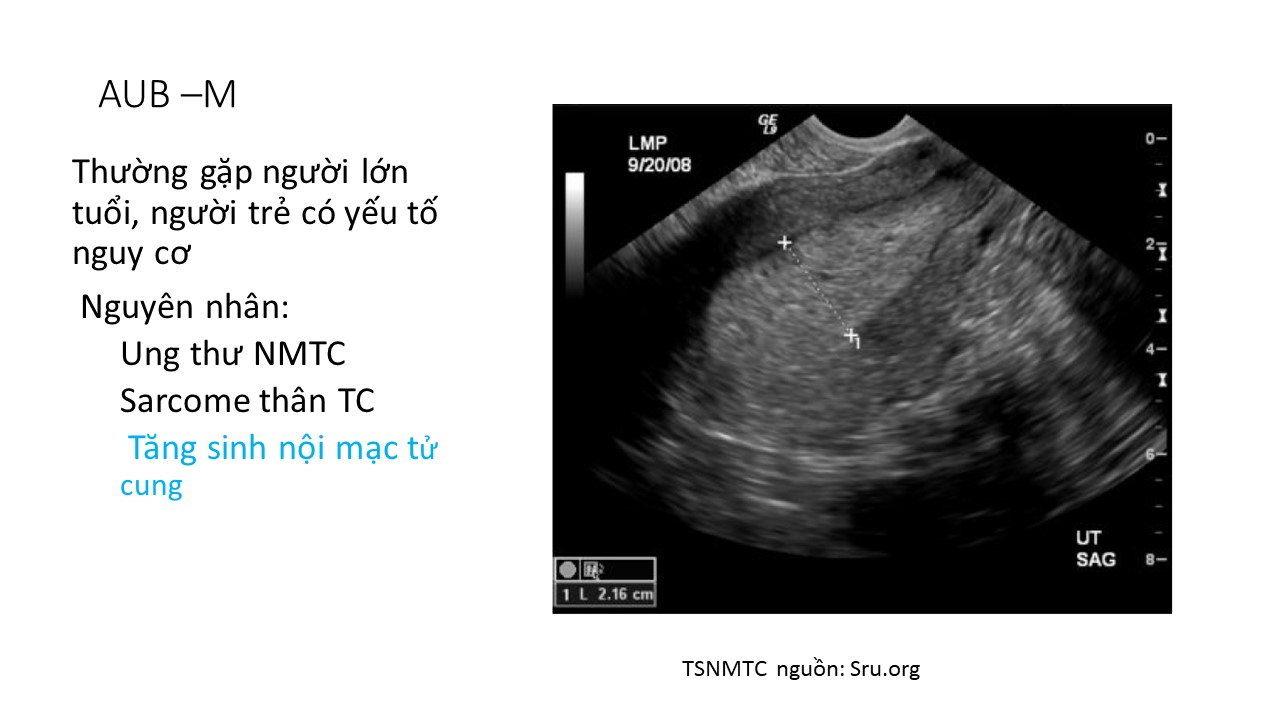

Tiếp cận bệnh nhân xuất huyết tử cung   sau mãn kinh

BS. Lê Hồng Cẩm